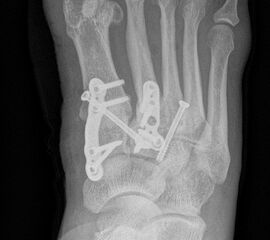

Die Korrektur des Spreizfußes und die Stabilisierung des TMT I ist das zentrale Element zur Entlastung des TMT II und III Gelenks. Dadurch kann die Lastachse wieder auf den ersten Strahl geführt werden. Aus Gründen der Stabilität sollte die Indikation zu einer Lapidusarthrodese großzügig gestellt werden. Eine TMT II und ggf. TMT III Arthrodese wird dann unter Berücksichtigung des Metatarsalindex unter Längenerhalt oder leichter Kürzung durchgeführt. Beim Pes metatarsus adductus kann der Eingriff mit einer Achskorrektur durchgeführt werden, um die Adduktionsstellung des Mittelfußes zu korrigieren (Abb. 9 und 10).

Zum Lesen der Bildbeschreibung und zur Vollansicht bitte die Bilder anklicken. Bilder: C. Hase

• Temporäre Fixierung mit 1,6 K-Drähten, BV- Kontrolle. Bei korrekter Stellung definitive Osteosynthese entweder mit je 2 Kompressionsschrauben, Platten oder Klammern.

• Die mechanisch stabilste Situation ist mit dorsalen winkelstabilen Platten, optional mit Kompressionsschraube zu erreichen 3.